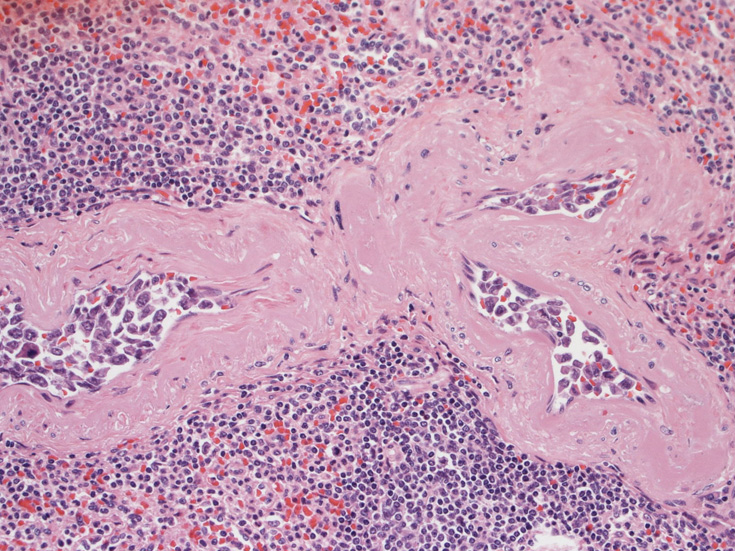

脳;くも膜下腔の小動脈内, 脳白質の細血管内に腫瘍細胞が充満している。

血管腔内に選択的に悪性リンパ腫細胞が増殖することを特徴とする節外性large B-cell lymphomaのまれなタイプ。WHOの定義ではBリンパ球の腫瘍であること, 血管内に腫瘍細胞が限局していることを診断の要件としている。歴史的には血管内皮の腫瘍性増殖とされneoplastic angioendotheliomatosisという用語が使用されてきたが, 1985年Moriらが免疫組織学的手法により増殖細胞がリンパ球あることを明らかにした*1

生検組織により血管内腔を塞ぐように大型異型リンパ球が増殖していることを確認することが診断の要件である。血管内増殖の病変分布が本病型では, 脳, 肺, 肝, 腎, 副腎, 皮膚, 骨髄など特有である。しかし大細胞型B細胞リンパ腫にはこのような臓器を選択的に侵襲するが, 血管内腔には増殖しないものがあることに留意が必要である。